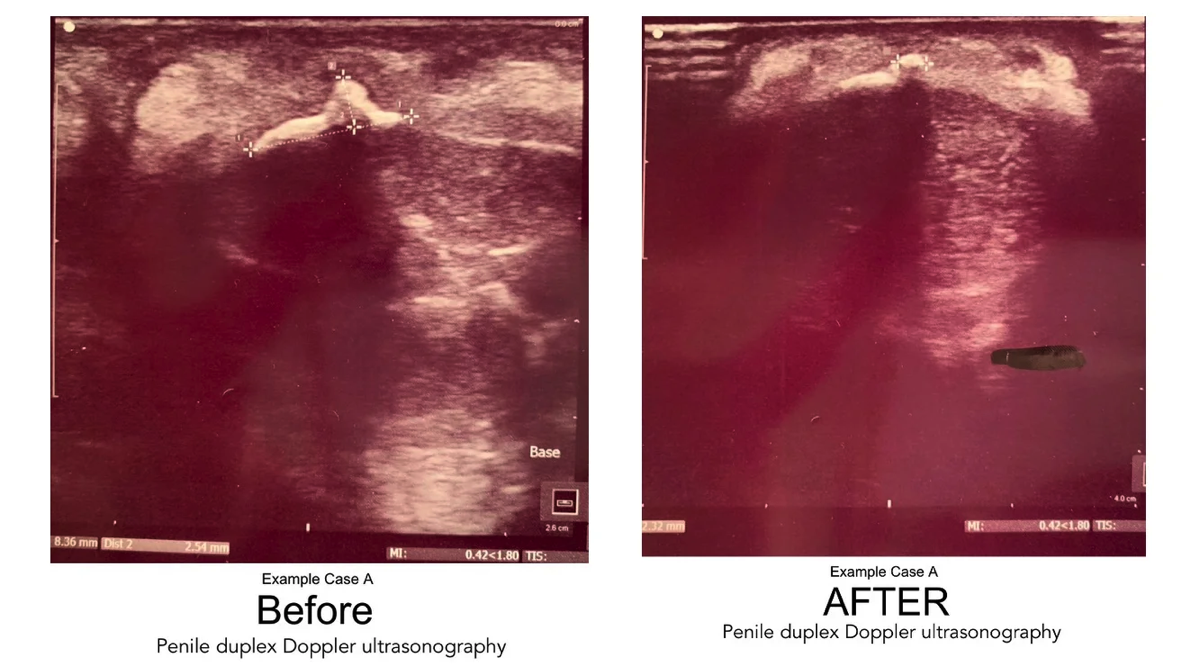

Calcified Plaque: Before & After Sonogram Images

Following are examples of "before and after" duplex sonogram images of ExoSurge® Peyronie's patients with calcified plaques. The reduction of calcified plaques is readily apparent, even to an inexperienced layperson. As far as we are aware, these photos are the first sonographic evidence of a visible reduction in calcified Peyronie's plaque from conservative therapy in the history of urology.

A database search using The Clinic’s Electronic Health Records (EHR) system was completed extrapolating patient medical charts with the diagnosis of PD and undergoing treatment between the dates of January 1, 2018, and March 6, 2020. Patient charts were included when they were found to have identifiable and measurable plaque with no less than two duplex doppler ultrasound diagnostic tests within that timeframe providing a pre-treatment ultrasound and a post or intra-treatment ultrasound for comparison. Of these patients, 101 were found to be consistent in receiving treatments during this timeframe. Those excluded were patients who had not been seen in the clinic within three months or more prior to the post or intra-treatment ultrasound tests and considered inconsistent with treatment.

Upon further review it was determined that within this patient sampling of 101, some pre-treatment recordings of the duplex doppler ultrasound diagnostic test was not complete and/or not comparable in recording to the post and/or intra-treatment ultrasound and therefor were not considered a good comparison. These patient charts were removed from the study leaving a total of 70 patient charts for comparison. All duplex doppler ultrasound diagnostic testing during the listed dates was completed by an independent, outside source on site at The Clinic.

Data retrieved from each duplex doppler ultrasound included degree of curve, identification of venous leak, identification of arterial insufficiency, erection grade, size of plaque, and consistency of plaque as either calcified or non-calcified.

A beginning baseline duplex doppler ultrasound analysis that included up to three measurable pieces of plaque was compared to a follow up duplex doppler ultrasound for measurable changes. Data retrieved from both the initial and final duplex doppler ultrasounds included findings of plaque. Plaque size was recorded in a 3-dimensional format in millimeters. Consistency of plaque was recorded as calcified or non-calcified. Penile curvature was identified in degree of curvature, which was then divided into two classes: curvature greater than or equal to 30 degrees and a curvature less than 30 degrees.

For the baseline duplex Doppler ultrasonography, the total number of pieces counted were 66. Of these, 52 were non-calcified and 14 were calcified. On the follow up duplex Doppler ultrasonography, the total number was 58. Of these, 48 were non-calcified and 10 were calcified. The reduction in the number of calcified plaque pieces was 28.6%.

The total plaque size measured with the baseline duplex Doppler ultrasonography in Area One was 302.9 mm3 and the follow up duplex Doppler tally in Area One was 55.7 mm3, representing an 81.5% reduction in penile plaque for the 70 patients.